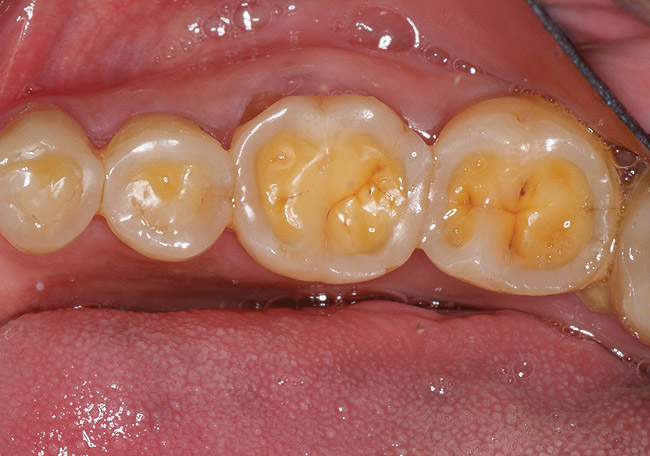

If a patient has risk factors that can contribute to dental erosion, an examination will reveal clinical signs and symptoms of dental erosion. It is unlikely that dental erosion will be seen without other contributing factors. Tooth wear and abrasion typically occur in combination with dental erosion. In the clinical evaluation of tooth surfaces for the diagnosis of erosion, what is typically seen are smooth, shiny surfaces of the teeth where the usual anatomic form of the tooth should be. In patients ingesting very acidic diets, the facial surfaces of anterior teeth are very smooth, and if the beverages being ingested have high sugar content, these teeth may have caries at their facial gingival margins (Figure 1). The occlusal surfaces of posterior teeth in the more advanced stages of erosion due to regurgitation may have extensive exposed dentinal areas with loss of anatomic form (Figure 2). In some cases, the chemical erosion combined with toothbrush–toothpaste abrasion can remove all the enamel, leaving only the dentin exposed (Figure 3). These teeth may exhibit sensitivity. Posterior teeth with restorations may demonstrate fillings that are higher than the surrounding occlusal surfaces of the enamel. Anterior teeth may demonstrate more incisal translucency due to tooth loss at the incisal edge. In patients with the eating disorder bulimia nervosa, who vomit, the hydrochloric acid causes extensive damage to the lingual surfaces of the anterior teeth, where the enamel is lost, leaving exposed dentin (Figure 4).

Figure 3  In a patient who smoked a pipe, the nicotinic acid causing tooth erosion was accentuated by the use of a highly abrasive smoker’s toothpaste. Some of the teeth have been restored with bonded composite resin.

Figure 3